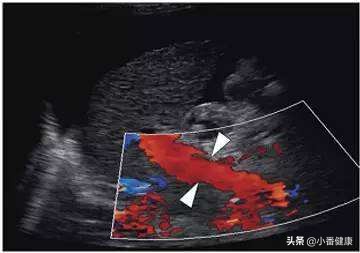

长期熬夜还很伤眼,久视伤身。眼睛是人类心灵的窗口,当遇到用眼疲劳时最好可以瞭望远方,让眼睛得到休息也可以减少肝脏负担。还有前面提到的,平躺静卧其实要比人在站立时,流经肝脏的血液更丰富,所以为了让肝脏获得更丰富的血液营养,无论是乙肝病毒携带者还是乙肝患者,都要记住良好休息时间,累了就要静卧休息,可以增加肝脏养分。